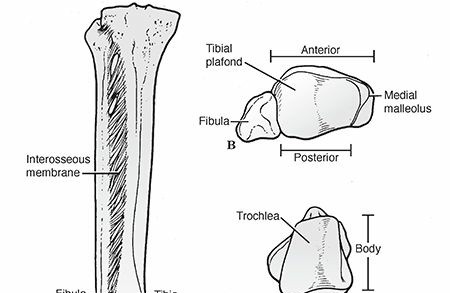

Malunion of the Talar Neck

Talar neck malunions are biomechanically analogous to intracapsular femoral neck fractures. The initial trauma often disrupts the delicate retrograde blood supply (artery of the tarsal canal, branches of the dorsalis pedis), leading to osteonecrosis (AVN) of the talar body.

Union typically occurs with the distal fragment (talar head) in rotation, medial deviation, and dorsal displacement, producing a complex varus or valgus deformity. Valgus deformity is more common, presenting with the head deviated medially and dorsally.